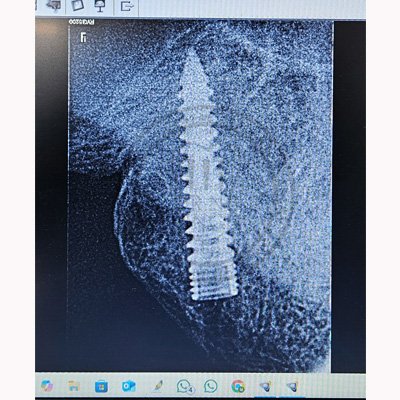

Case – 11 Baleram